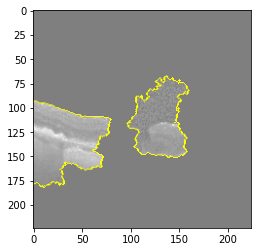

Fig 6, 7, 8 and 9 depicts the visualization of correct predictions by our proposed CNN model where fig 6 is class CNV, fig 8 is class DME, fig 7 is DRUSEN and finally, fig 9 is NORMAL. Here the first photo in every class is the original image. The LIME map of our suggested model’s prediction is shown in image B whereas in image C the positive region is highlighted in specific sections on the original image. For Image D we have increased the number of features from 5 to 10 thus more regions have been predicted as the positive region which is highlighted in green. After increasing the features from 5 to 10, some of the regions are predicted wrongly. The red regions represent the output of incorrect prediction. The following image represents the Grad-CAM heatmap highlighting the regions with our model’s prediction.